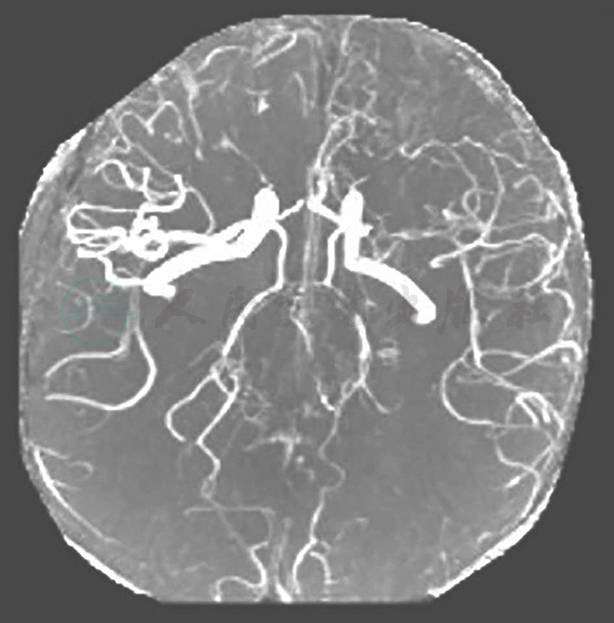

复查CRP、ESR较前上升,头颅MRA(图1)提示血管病变较前加重,考虑病情活动,建议应用TNF-α抑制剂,有助于控制病情发展并协助激素减量,患者及家属拒绝,遂予甲泼尼龙500mg×3d冲击治疗,后加强免疫抑制剂治疗,方案调整为醋酸泼尼松50mg qd+环磷酰胺600mg q2w+吗替麦考酚酯1750mg每天分为两次口服,并辅以降压、降糖、保肝等治疗,出院后患者糖皮质激素仍难以减量至35mg qd以下,减量后会再发头痛及下肢疼痛,伴有红细胞沉降率及CRP升高。

图1 头颅MRA(2015年12月)

左侧大脑中动脉中、重度狭窄或闭塞;双侧大脑前动脉、右侧大脑中动脉、基底动脉及双侧椎动脉、双侧大脑后动脉多发节段性管腔狭窄